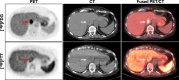

Background: Poly (ADP-ribose) polymerase inhibitors (PARPi) are approved for Breast Cancer gene (BRCA)-mutant HER2- breast cancer, and there is clinical interest in expanding indications to include homologous recombination deficient (HRD) breast cancers. Yet, response in these populations remains variable, suggesting clinical utility in developing a better biomarker to select patients for PARPi and predict response. Here, we evaluate a radiolabeled PARPi, [18F]FluorThanatrace ([18F]FTT), as a functional biomarker of PARPi response in breast cancer.

Methods: A single-arm prospective observational trial was conducted at the University of Pennsylvania. [18F]FTT-PET uptake was measured in 24 women with untreated primary breast cancer and correlated with tumor HRD score. In a separate cohort of ten subjects with metastatic HER- breast cancer, [18F]FTT-PET uptake was measured at baseline and after a short interval on a PARPi (a measure of drug-target engagement) and correlated to progression free survival (PFS).

Results: Here we show that baseline [18F]FTT-PET uptake does not correlate to HRD tissue score, supporting that [18F]FTT provides distinct information from genetic features. Baseline [18F]FTT-PET uptake and the change in uptake from baseline to after PARPi initiation significantly correlates to PFS in woman with breast cancer who received a PARPi (ρ = 0.74, P = 0.023 and ρ = -0.86, P = 0.012, respectively).